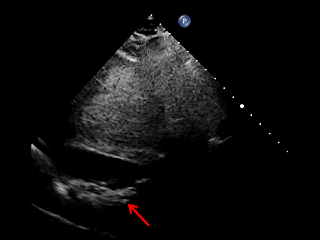

释放后超声

剑下双房心切面